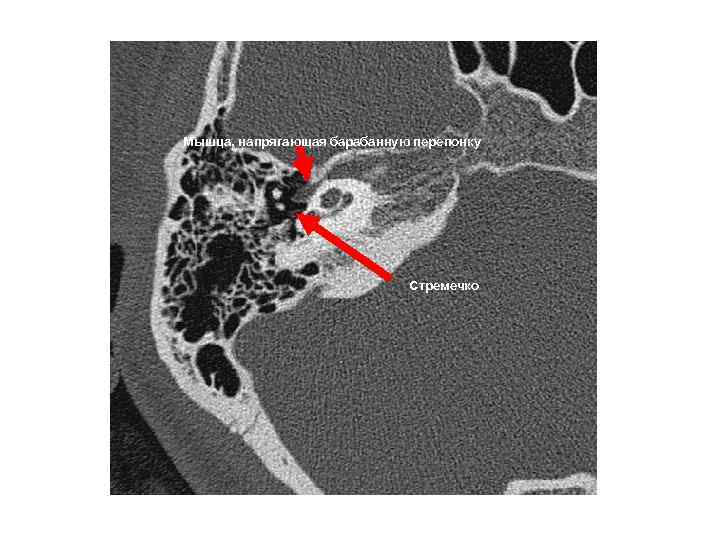

Мышца, напрягающая барабанную перепонку Стремечко Мышца, напрягающая барабанную перепонку Стремечко